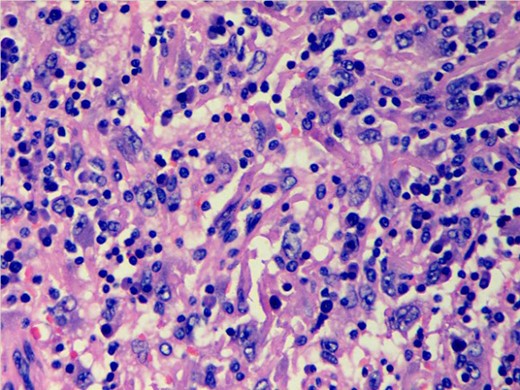

A 40-year-female patient presented with a large left axillary mass located in close proximity to the left breast (Fig. 1) which had gradually increased to its present size over a period of 3 months. There was no associated history of sweating or loss of weight. On examination, the mass was 13 × 11 cm in size at the level of anterior axillary nodes, firm in consistency with well-defined margins. No mass was palpable in either breast or any other lymph node in the entire body. The patient had undergone fine needle aspiration cytology at a peripheral hospital which revealed metastatic adenocarcinoma and, thus, was suspected to arise from a primary in the breast. However, diagnostic mammogram also failed to reveal any suspicious lesion in the breasts. Tru-cut biopsy of the lesion was performed, which revealed lymphocytes scattered throughout the tissue and no definite diagnosis was possible. Thus, excision biopsy of the mass was planned (Fig. 2). The cut surface of the surgical specimen was homogeneously brownish chocolate with central areas of hemorrhage. The section showed encapsulated mass covered by a thick fibrous capsule. The internal organization of the mass resembled a lymph node showing numerous follicles-like structures at the periphery. The center of the follicle was occupied by blood vessel; with swollen proliferating endothelial cells. The predominant cells in these follicles were mature small lymphocytes, large transformed cells and plasma cells (Fig. 3). At places, there were areas of hyalinization. Interfollicular areas showed numerous single and binucleated plasma cells intermingled with mature small lymphocytes, transformed lymphoid series cells, cells morphologically indistinguishable from Reed Sternberg cells, histiocytes and fibroblast. These histological features were suggestive of Castleman's disease showing patterns of both hyaline vascular type and plasma cell type (angiofollicular lymphoid hyperplasia). However, the second opinion of an experienced pathologist was taken who reported these findings to be suspicious of HS. To clear the diagnostic dilemma, immunohistochemistry (IHC) studies were done. All IHC markers were evaluated in the context of appropriate positive and negative controls. The tumor cells expressed CD31 and CD163 (Fig. 4) and were negative for S-100 protein, CD68, CD1a, CD23, CD21, cytokeratin, EMA, CD20, CD3, CD30, SMA, ERG, CD34 and CD35. Thus, the diagnosis of HS was clinched. Computed tomography scans of the thorax and the abdomen did not reveal any other site of lymphadenopathy. Bone marrow biopsy also failed to reveal any lymphoid infiltration. The patient is planned to receive six cycles of the standard Cyclophosphamide, Doxorubicin, Vincristine, Prednisolone chemotherapy.

Photomicrograph showing scattered discohesive large cells with pleomorphic nuclei (H&E stain; ×400).

Histological features consist of discohesive large cells with pleomorphic nuclei and abundant cytoplasm; however, a light microscopy alone is unreliable in establishing the diagnosis. Thus, immunophenotypic studies are essential to establish the diagnosis. Markers once regarded to be specific for histiocytic differentiation, such as α-1-antitrypsin, α-1-antichymotrypsin, lysozyme and CD68, have been shown to have low specificity as they can be positive in a wide variety of neoplasms [7]. Moreover, McHugh and Miettinen [8] reported both CD68 and α-1-antitrypsin immunoreactivity in melanoma with similar frequency to that of traditional melanoma markers (S-100, HMB-45), although the staining is usually not as intense. CD163 has recently been studied in a variety of benign and malignant tissues and shows almost exclusive expression in the cells of monocyte/macrophage lineage. In concordance with these studies, strong cytoplasmic immunoreactivity for CD163 was present in the case under discussion confirming histiocytic differentiation. Vos et al. [9] studied five cases of HS and concluded that CD163 appears to be a specific histiocytic marker and is important in establishing the diagnosis of HS. Most of the cases in the literature are reported to be a CD68 positive. However, in this patient, IHC markers were negative for myeloid cells (CD34), accessory/dendritic cell markers (CD1a, CD21 and CD35), CD30, S100; and metastatic carcinoma (epithelial membrane antigen). Thus, the diagnosis of HS was established.